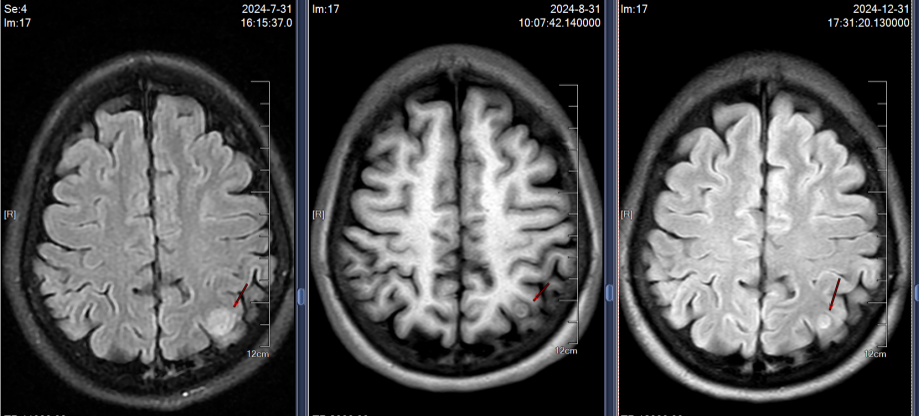

2024年7月30日胸部CT示:左上肺术区新增结节,两肺多发实性结节较前增多,肝S7新增结节;7月31日头颅MRI示左侧顶叶、小脑半球新增转移灶。结合影像及病史,确诊为ALK阳性晚期NSCLC复发伴多发转移(图1)。

影像学随访显示肺部、肝部的病灶完全消失,脑部的病灶缩小稳定;